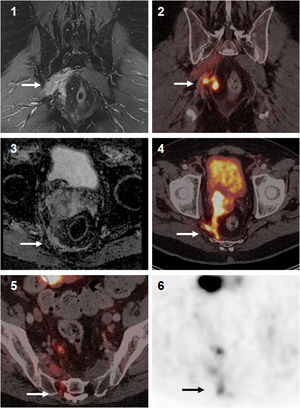

The contrast enhanced mpMRI demonstrated a locally advanced prostate cancer with infiltration of mesorectal fascia, right seminal vesicle and, besides, oedema with contrast enhancement of the right piriformis muscle and thickening of the nerval roots of the plexus sacralis indicated tumor infiltration, albeit mpMRI has limitations for the correct identification of mucinous parts of prostate carcinoma. In addition, mpMRI revealed multiple lymph node metastases in the pelvis. Despite morphologically extensive tumor involvement of the pelvic organs and the known diagnostic superiority of mpMRI over PET/CT regarding the soft tissue evaluation, a contrast-enhanced, whole-body [18F]PSMA-1007 PET/CT scan had to follow for a better tumor delineation in the area of sacral plexus, as this plays a pivotal role for the quality of life for patients as well as a correct radiotherapy planning (determination of gross tumor volume = GTV). The PSMA imaging revealed a locally advanced prostate cancer with infiltration of adjacent structures and organs involving right seminal vesicle, reaching to the anterior wall of the rectum and metastasis to pelvic lymph nodes and a further solitary metastasis to right scapular bone (Fig. 1). The tumor findings in the pelvis exhibited in total a moderate PSMA uptake with an SUVmax of up to 18.1, whereas the metastases to lymph nodes showed rather low PSMA uptake with an SUVmax of up to 1.9. An intensive [18F]PSMA-1007 uptake was seen in the scapular bone with an SUVmax of up 34.0 with no CT correlate. Clinically most significant [18F]PSMA-1007 finding was the identification and also correct tumor delineation in the area of sacral plexus, as [18F]PSMA-1007 imaging here adds further information to the MRI findings (Fig. 2).2,3 In the following clinical course, the patient received a PSMA-guided, palliative radiotherapy of the pelvic parts of malignant spread in combination of a systemic androgen deprivation therapy (ADT). The scapular lesion underwent osteoblastic changes after the initiation of ADT, which was interpreted as a validation of malignancy.

Synergistic effect of multiparametric MRI and [18F]PSMA-1007 PET/CT imaging: Better delineation and discrimination of the local tumor extent (1,2). Due to the lack of ADC descent on MRI (3), it is not possible to distinguish reliably between infiltration or possible oedema. PSMA PET/CT (4) suggests tumor infiltration due to PSMA expression. In addition, [18F]PSMA-1007 imaging (5, 6) indicates tumor infiltration of the sacral plexus, which escapes the detection by the standard MRI protocol.